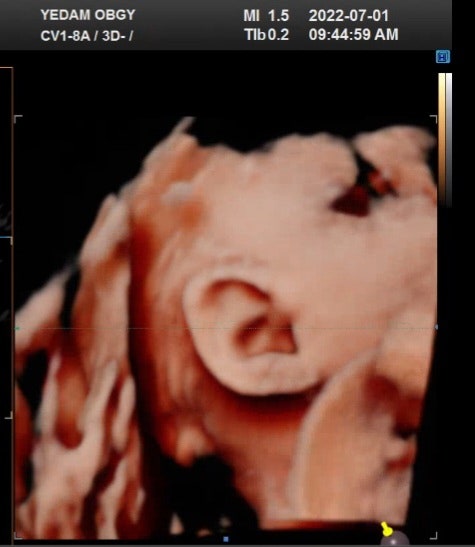

[임신 29주차] 정기검진/임신 29주차 증상, 태동/임신 30주차 배크기/딸랑이 만들기

안녕하세요! 다 큰 어른이의 오늘 기록, 도나도나입니다^^ 임신 29주차 정기검진 7.1.금요일 대전 예담산부...